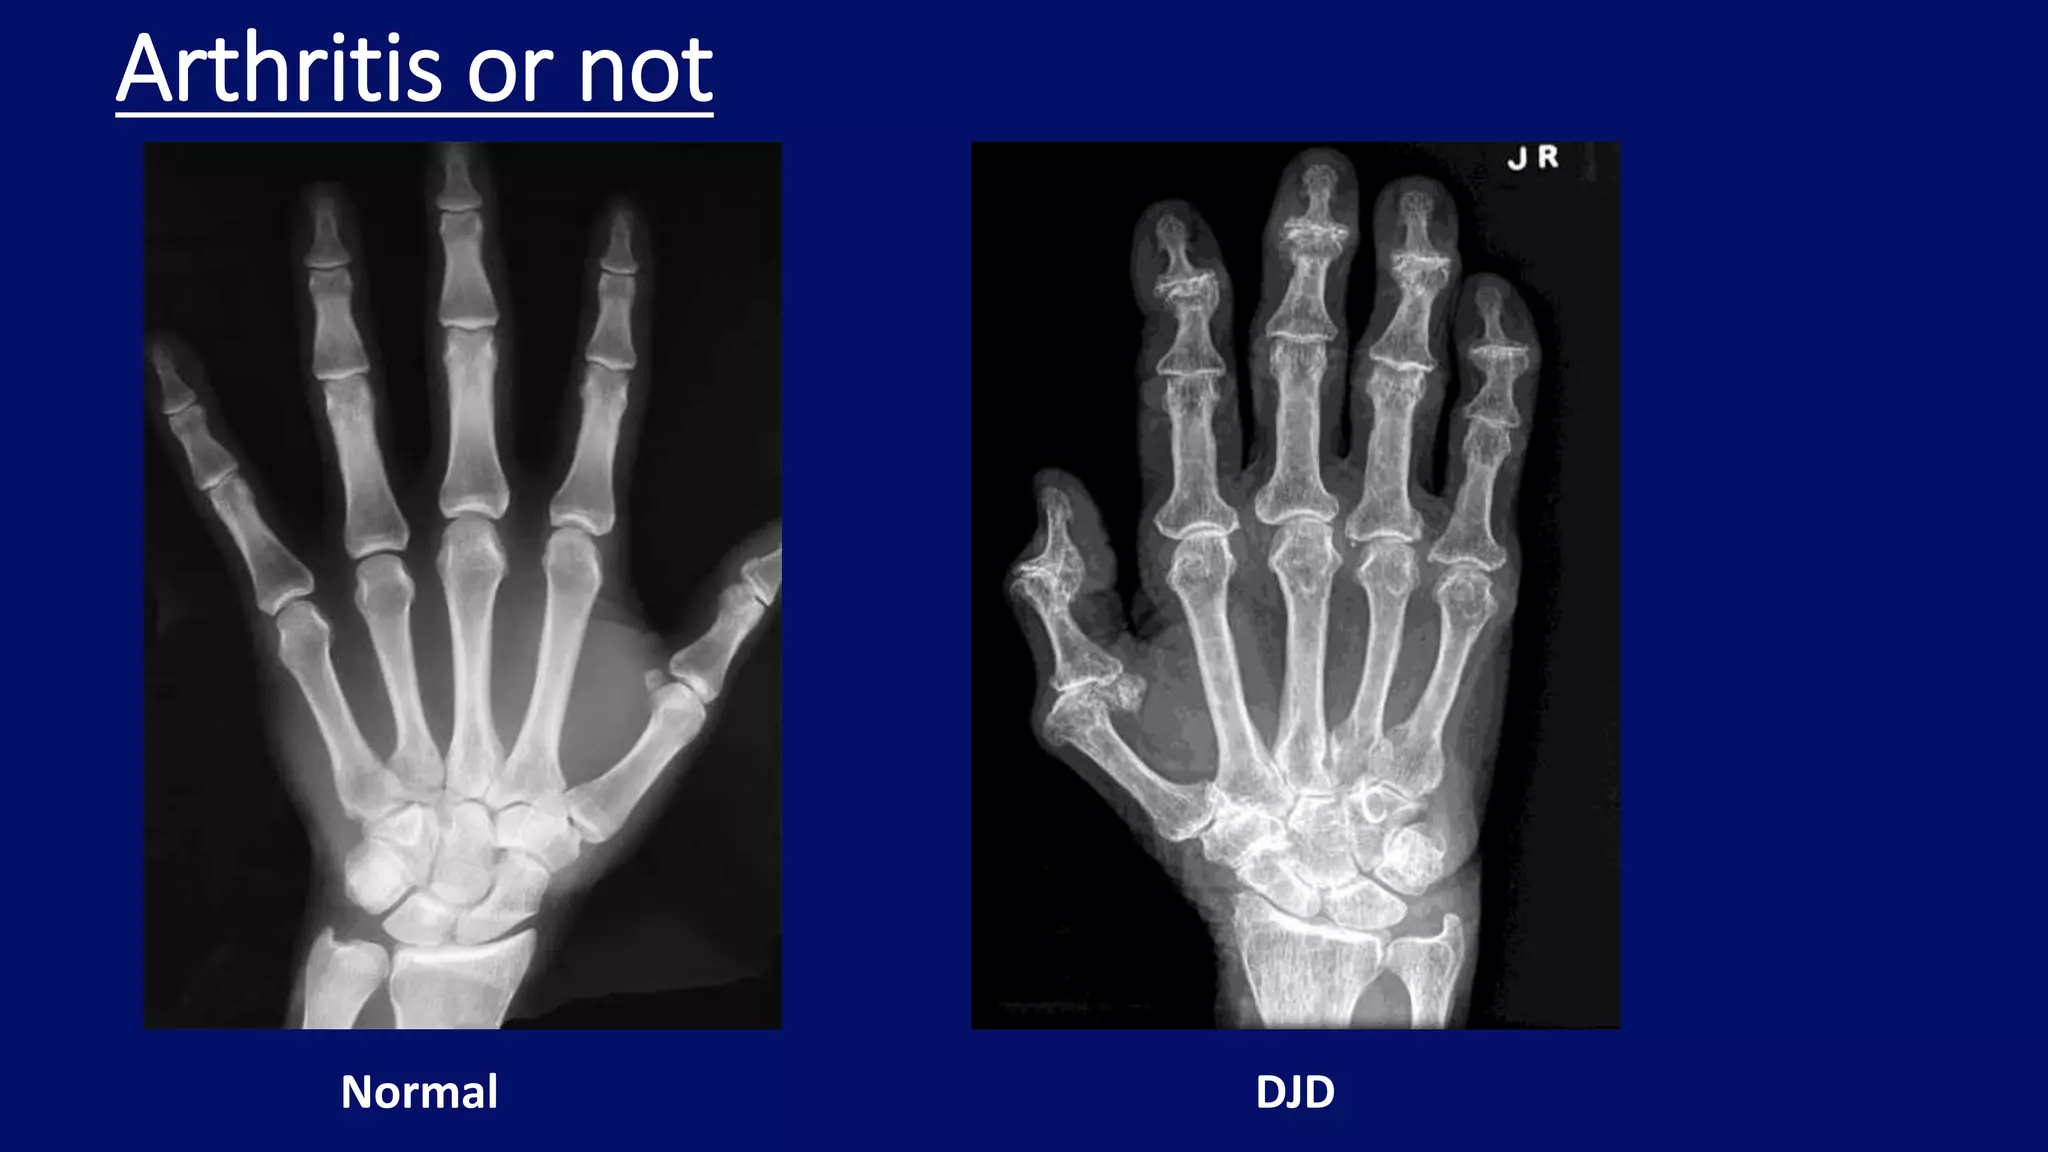

Scleroderma

• generalized systemic inflammatory connective tissue

disease of unknown cause

• strong female predilection (F:M 3:1)

• frequent involvement of the musculoskeletal system

• predominantly affects the fingers, wrists and ankles

• atrophy of the soft tissues at the tips of the fingers

• resorption of the distal phalanges

• subcutaneous and periarticular calcifications

• destructive changes of the small articulations

• flexion contractures

Radiographic features

Atrophy of the

soft tissues at

the distal

phalanges of

the index,

middle, and

ring fingers

R